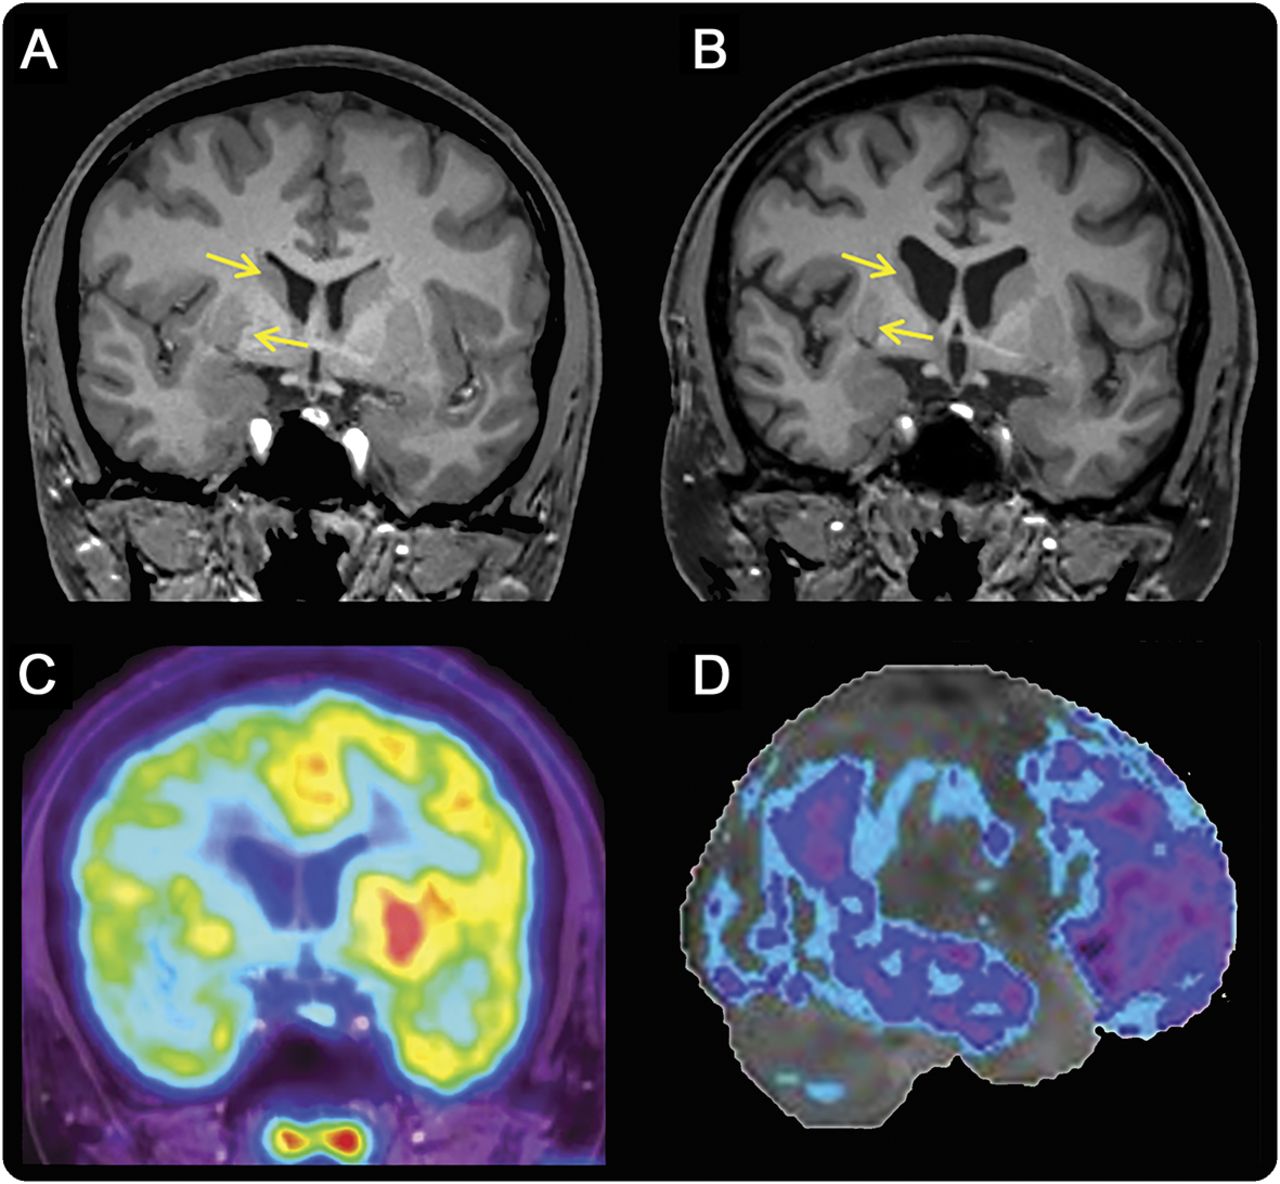

图

大脑的磁共振成像和发作的宠物

冠状t1加权磁共振成像从2015年2013 (A)和(B)显示进步的脑萎缩,右边比左边,最突出的纹状体(箭头)。从2011年最初的核磁共振正常。(18F] pet显示右半脑代谢减退主要包括纹状体(C)和额叶和颞叶(蓝色区域,D)。